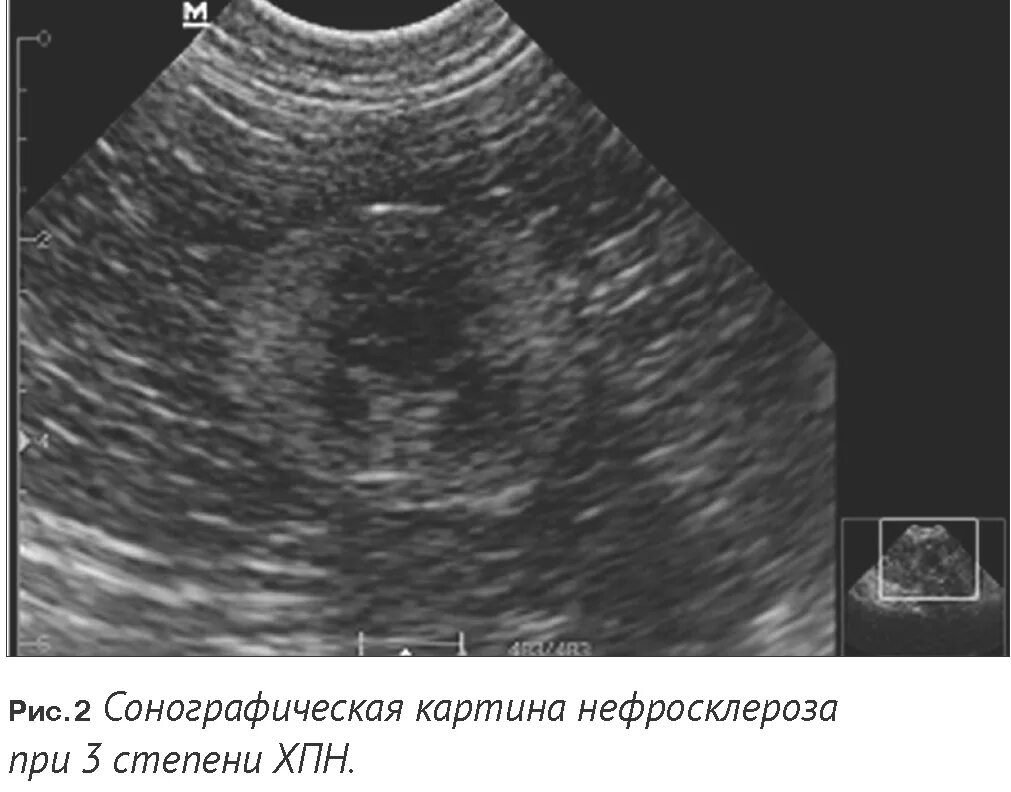

Нефросклероз почек на узи что это такое